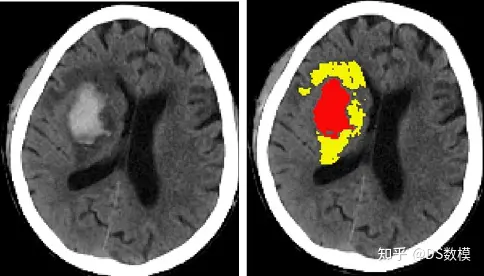

左图脑出血患者CT平扫,右图红色为血肿,黄色为血肿周围水肿

赛题提供了160例(100例训练数据集+60例独立测试数据集)出血性脑卒中患者的个人史、疾病史、发病及治疗相关信息、多次重复的影像学检查(CT平扫)结果及患者预后评估,该部分信息可在“表1-患者列表及临床信息”中查询。如图1为脑出血患者CT平扫,红色为血肿区域,黄色为水肿区域。赛题提供影像学检查数据,包括各个时间点血肿/水肿的体积、位置、形状特征及灰度分布等信息。体积及位置信息可在“表2-患者影像信息血肿及水肿的体积及位置”中查询。形状及灰度分布信息可在“表3-患者影像信息血肿及水肿的形状及灰度分布”中查询。